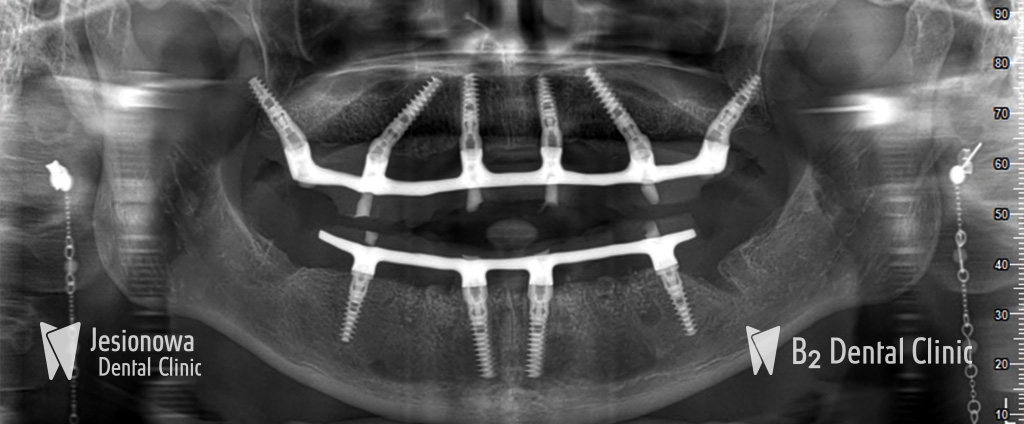

All-on-6 to metoda leczenia bezzębia polegająca na zastąpieniu brakujących zębów przy użyciu pojedynczego mostu mocowanego na stałe, obejmującego cały łuk zębowy przy użyciu 6 implantów zębowych i natychmiastowego ich obciążenia.

Metoda All-on-6 wymaga zastosowania jedynie 6 implantów w celu zastąpienia 14 zębów. Wprowadzenie 6 implantów w szczęce zapewnia optymalne koszty oraz przewidywalność leczenia.

Zabieg podnoszenia zatok szczękowych przy zastosowaniu metody All-on-6 nie jest konieczny. Specjalne pochylenie 4 implantów zapewnia odpowiednią stabilizację w łuku zębowym oraz ominięcie zatok szczękowych.

3. Wszczepienie implantów i praca protetyczna

Na tym etapie wszczepiamy 6 implantów do których zostanie przymocowana stała praca protetyczna. Zabieg jest całkowicie bezbolesny, a jego czas trwania wynosi średnio 90 min (bez dodatkowych zabiegów regeneracyjnych kości).